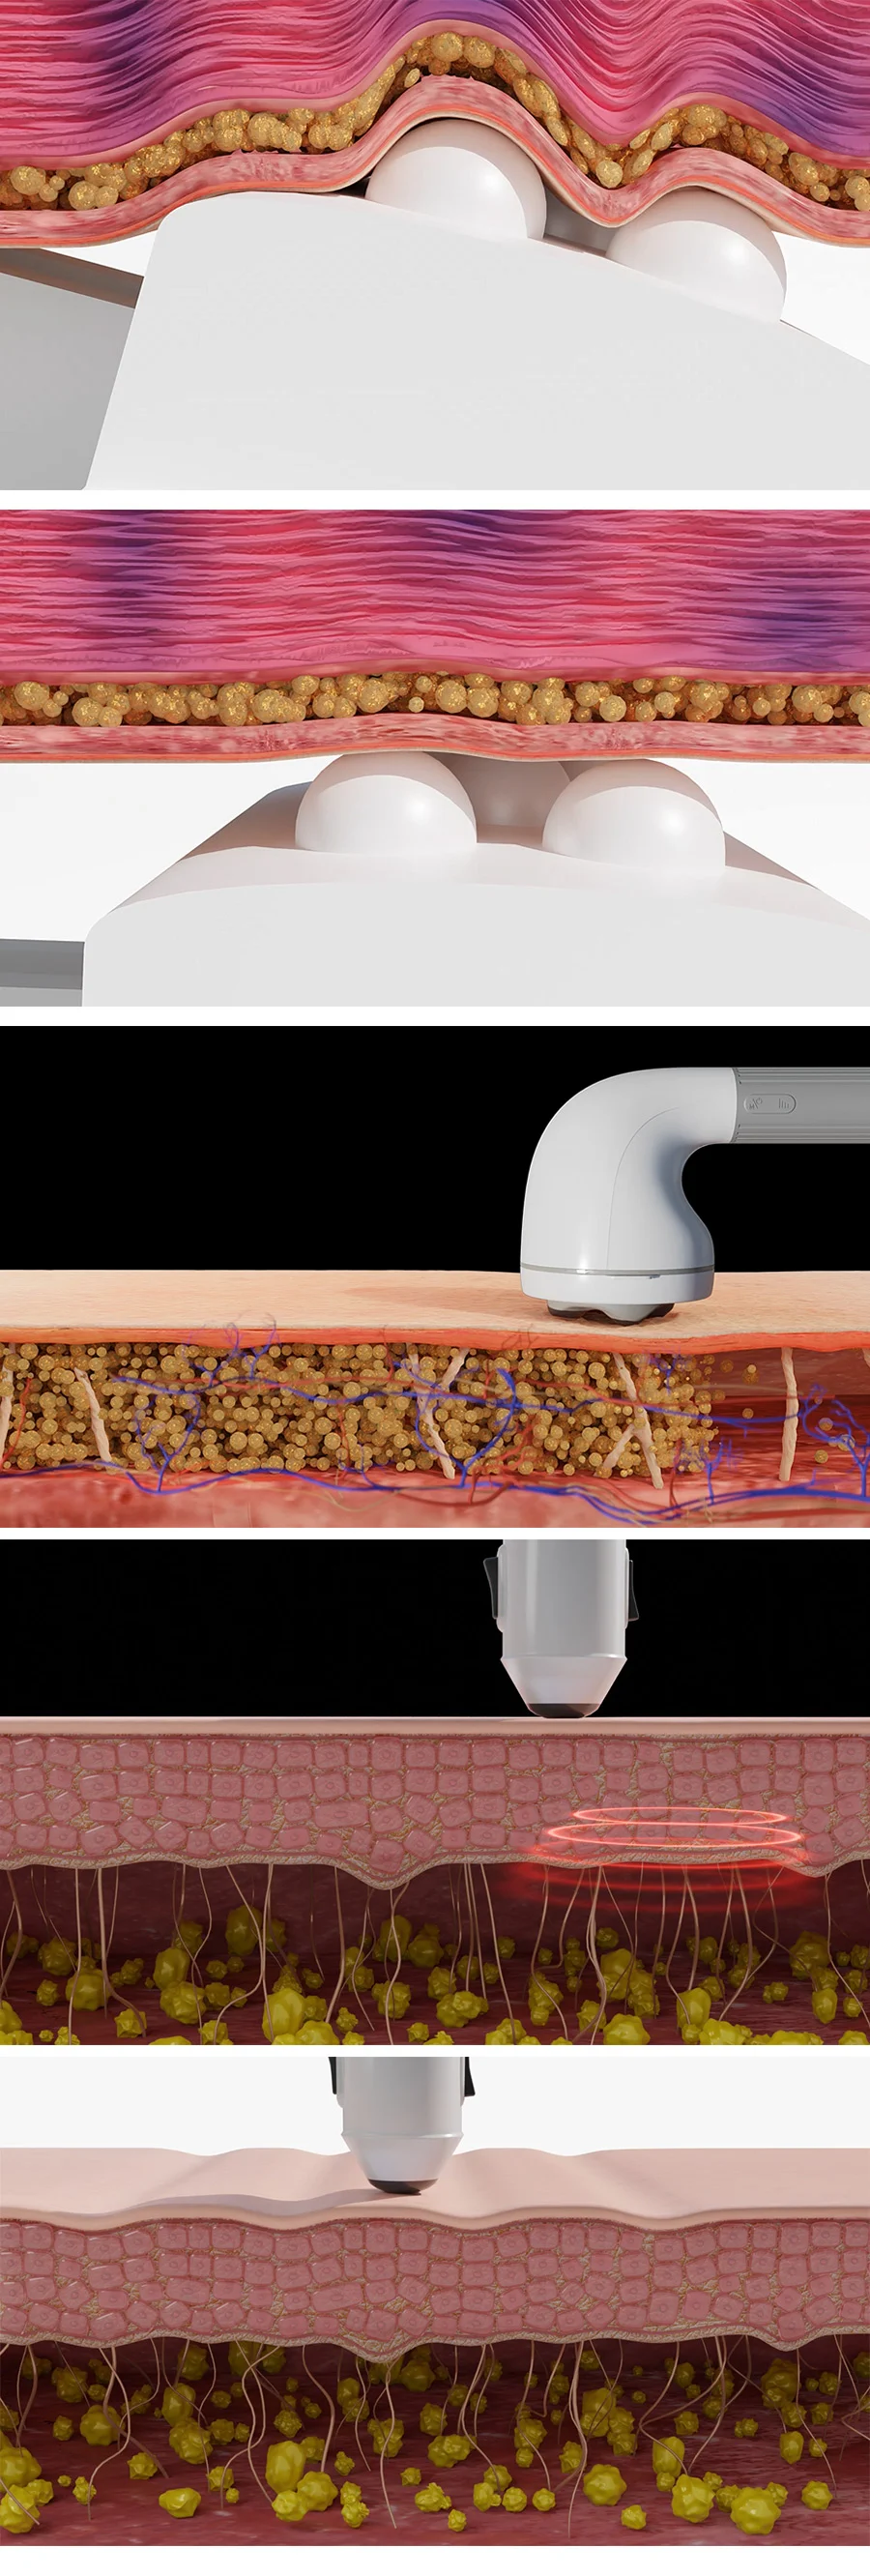

의학 관련 : 의료 효과,신체 해부학

의료, 의학 , 의료기기 시뮬레이션 제작

ex) 피부에 화장품이 스며드는 장면 ( 세포, 입자 등)

ex) 신체조직 혹은 신체안에서 변화&반응하는 시뮬레이션

ex) 의료기기의 원리